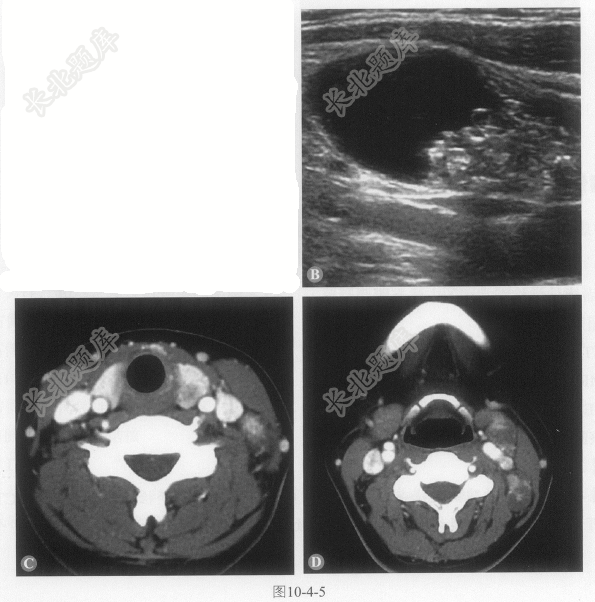

- 多项选择题2.该患者进行了超声及CT检查(图10-4-5,彩图10-4-5A),超声提示甲状腺左叶低回声为主肿物,形态不规则,回声不均匀,内可探及多个微小强回声光点及丰富血流信号,颈部可见低回声结节,内可见无回声区,CT可见甲状腺左叶边缘模糊结节,密度不均匀,颈部可见多发肿大淋巴结,明显强化,该病可能的诊断为: